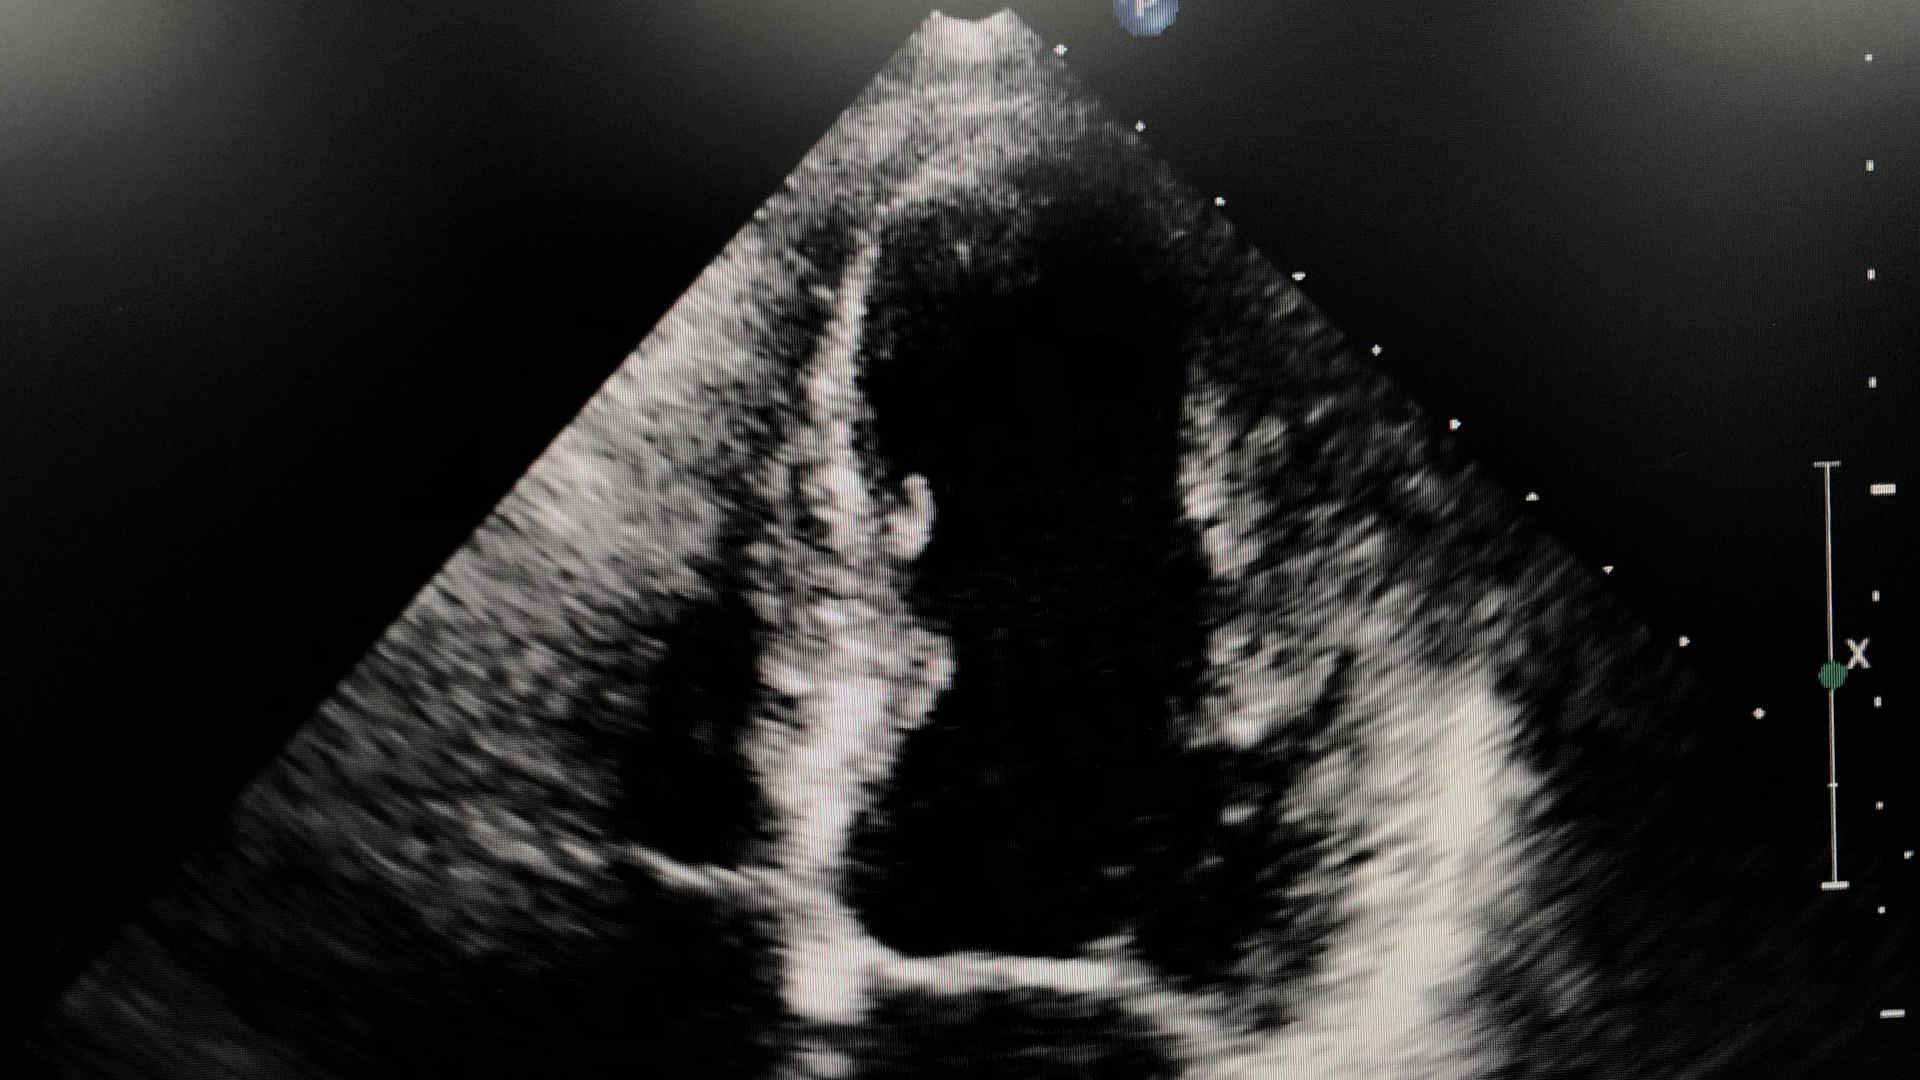

Prof Ary Serpa Neto (Melbourne) presents the results of the ACTiVE trial at CR Down Under 2025 in melbourne. ACTiVE investigates automated closed-loop ventilation in critically ill adults. Prof Danny McAuley (Belfast) delivers an independent editorial. Carol Hodgson (Melbourne) chairs a panel discussion between Anais Charles-Nelson (Melbourne), Shay McGuinness (Auckland) and Matthew Semler (Nashville).